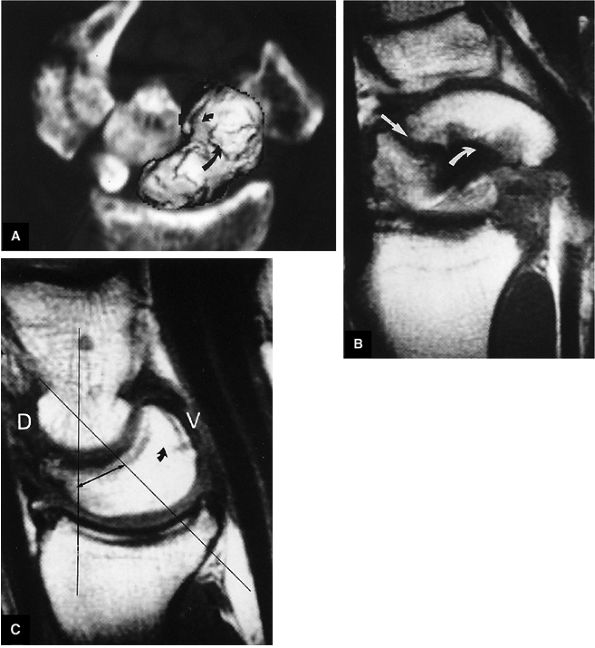

FIGURE 10.90 ● Scapholunate ligament tear with DISI. (A) Traumatic avulsion of the lunate aspect of the scapholunate ligament on a fast STIR coronal image. The scapholunate interval is widened with direct extension of fluid filling the tear site (large straight arrow). Ligament fibers are still attached to the radial aspect of the lunate (small straight arrow). Morphology is amorphous at the avulsed scaphoid remnant (curved arrow). (B) The capitolunate angle (arrow) is increased to 46°, and there is associated dorsal tilting of the lunate. (C) The scaphoid tilts palmarly with an increased scapholunate angle (arrow) of 142°.